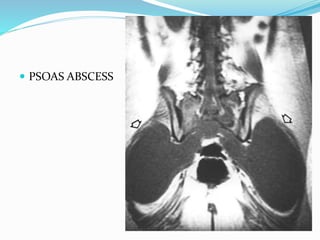

 NOTE: PUS CAN TRACK IN ANY DIRECTION

4.ALONG MUSCULOFASCIAL PLANES :

EX.PSOAS ABSCESS

 LUMBAR : PRE VERTEBRAL SWELLING/ PSOAS

ABSCESS / ABSCESS PRESENTING AT GROIN

 PSOAS ABSCESS

 PSOAS ABSCESS : EXTRAPERITONEALLY VIA KIDNEY

COLD ABSCESS  1.PARAVERTEBRAL ABSCESS : A SOFT TISSUE SHADOW CORRESPONDING TO AFFECTED VERTEBRA.  WIDENED MEDIASTINUM  RETROPHARYNGEAL ABSCESS  PSOAS ABSCESS